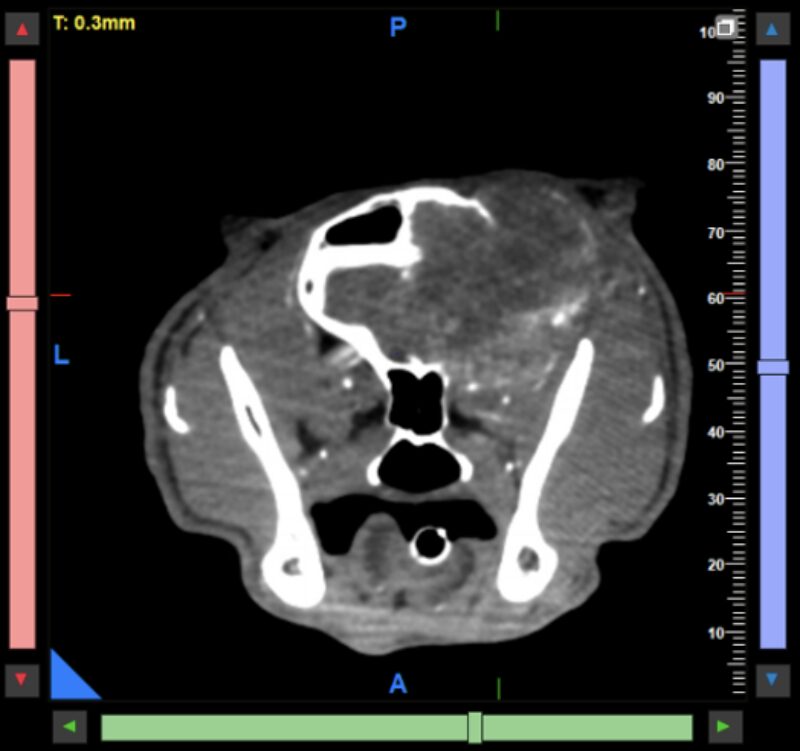

Kopf und Hals: Tumoren im und am Kopf lassen sich mit dem CBCT sehr präzise darstellen. Neben der exzellenten Beurteilung knöcherner Invasionen können auch Weichteilanteile zuverlässig abgegrenzt werden, was insbesondere für die präoperative Planung relevant ist. Kiefer- und Zahntumoren sowie komplexe dentale Erkrankungen profitieren weiterhin von der hohen Ortsauflösung des CBCT, die in diesen Bereichen einem klassischen Slice-CT überlegen sein kann. Bei brachycephalen Patienten hat sich das präoperative Dental-CT als Standard etabliert und ersetzt häufig eine Vielzahl konventioneller Dentalröntgenaufnahmen (Abb. 1 & 2).